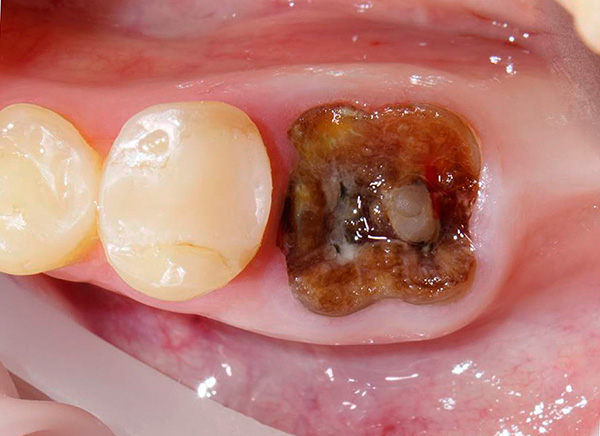

A volte la corona del dente è così gravemente danneggiata che rimane solo la radice del dente, che è corrosa dalla carie - in tali casi sorge la domanda di rimuovere questi residui "marci". Spesso ci sono lesioni fastidiose: ad esempio, un pezzo di dente può rompersi durante il pasto e una scheggiatura (o una crepa) a volte va in profondità sotto la gengiva - in questo caso, può anche essere richiesta l'estrazione della radice del dente.

Dal punto di vista di un dentista, la situazione in cui un paziente cammina per anni con un dente cariato, distrutto alla base, appare come segue: questa persona non si dispiace per se stessa. Il fatto è che in questi casi, le radici dei denti devono essere rimosse urgentemente (vedi l'esempio nella foto sotto).

Il motivo è semplice: le radici marce sono un focolaio di infezione e più sono in bocca, più i problemi sono pronunciati e sono tutt'altro che limitati a alitosi costante. Questi "marci" porosi come un aspirapolvere assorbono da soli batteri e particelle di cibo. Oltre al cibo in decomposizione, sui residui dei denti sono presenti anche placca difficile da rimuovere e quasi sempre tartaro sopra e sottogengivale, che causa sofferenza alle gengive.

In quasi il 100% di tali casi, si osserva un processo infiammatorio in cima alle radici marce, accompagnato da rarefazione del tessuto osseo, si forma un granuloma o una cisti. In poche parole, nella parte superiore della radice c'è un sacco purulento, che sta solo aspettando che le ali si spezzino con la formazione di un "flusso".